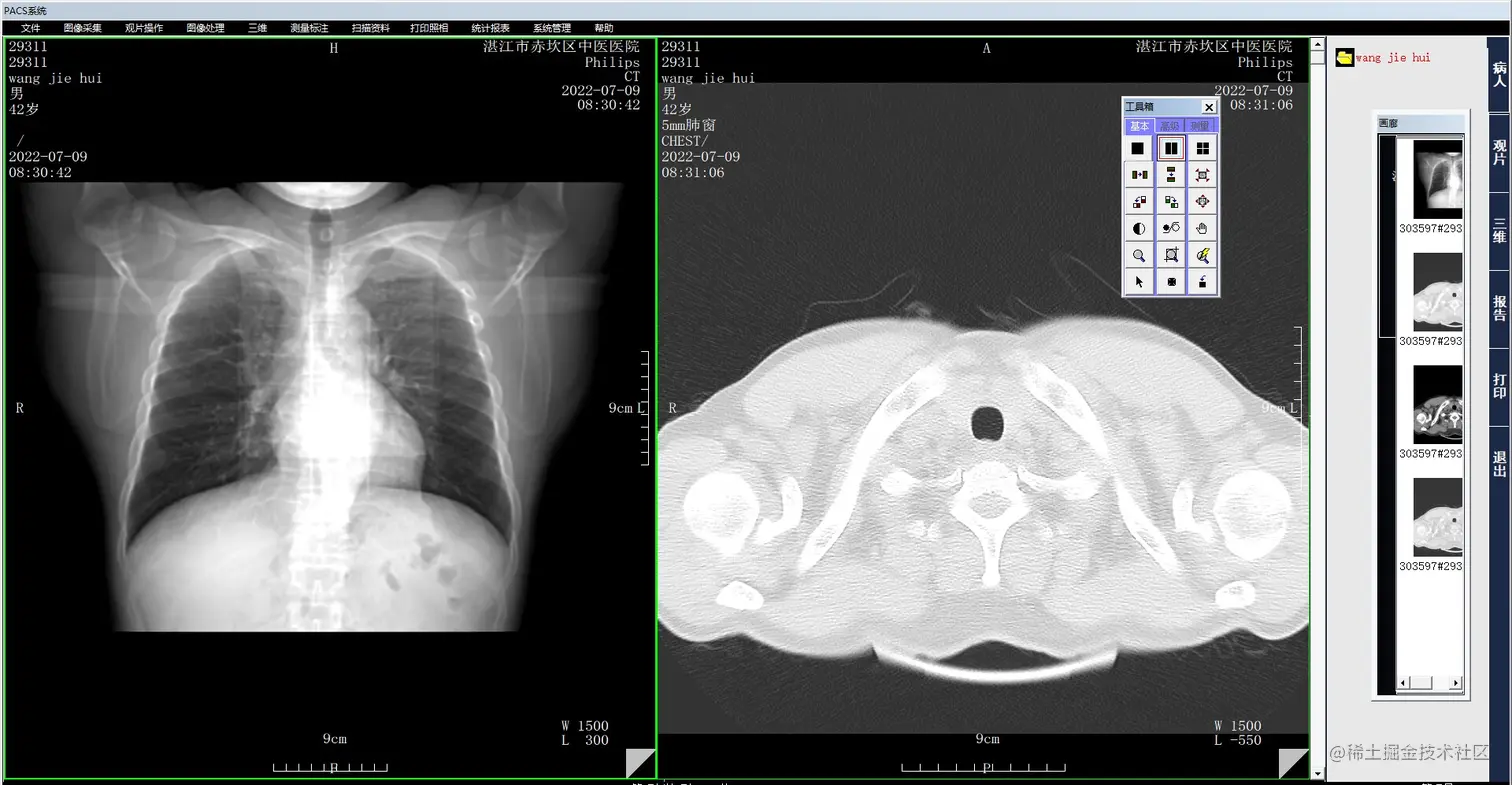

PACS系统是Picture Archiving and Communication Systems的缩写,意为影像归档和通信系统。它是应用在医院影像科室的系统,主要的任务就是把日常产生的各种医学影像(包括核磁,CT,超声,各种X光机,各种红外仪、显微仪等设备产生的图像)通过各种接口(模拟,DICOM,网络)以数字化的方式海量保存起来,当需要的时候在一定的授权下能够很快的调回使用,同时增加一些辅助诊断管理功能。它在各种影像设备间传输数据和组织存储数据具有重要作用。

1.png PACS系统源码特点:

• 覆盖院内大多数影像科室。可连接医院的多种影像设备:包括CT、MRI、CR/DR、DSA、ECT、PET、PET/CT、PET/MR、US、内窥镜、病理显微镜、ECG等;

• 高效的检查信息查询:可通过影像号、患者姓名、年龄、性别、检查时间、检查设备等多种查询条件迅速的获取查询患者;

8.png • 具有预约、登记、排队、收费、诊断报告、查询、统计、管理等功能;

• 提供多种高级影像后处理功能:(包括三维多平面重建、三维容积重建、三维表面重建、三维虚拟内窥镜、最大/小密度投影、心脏动脉钙化分析);